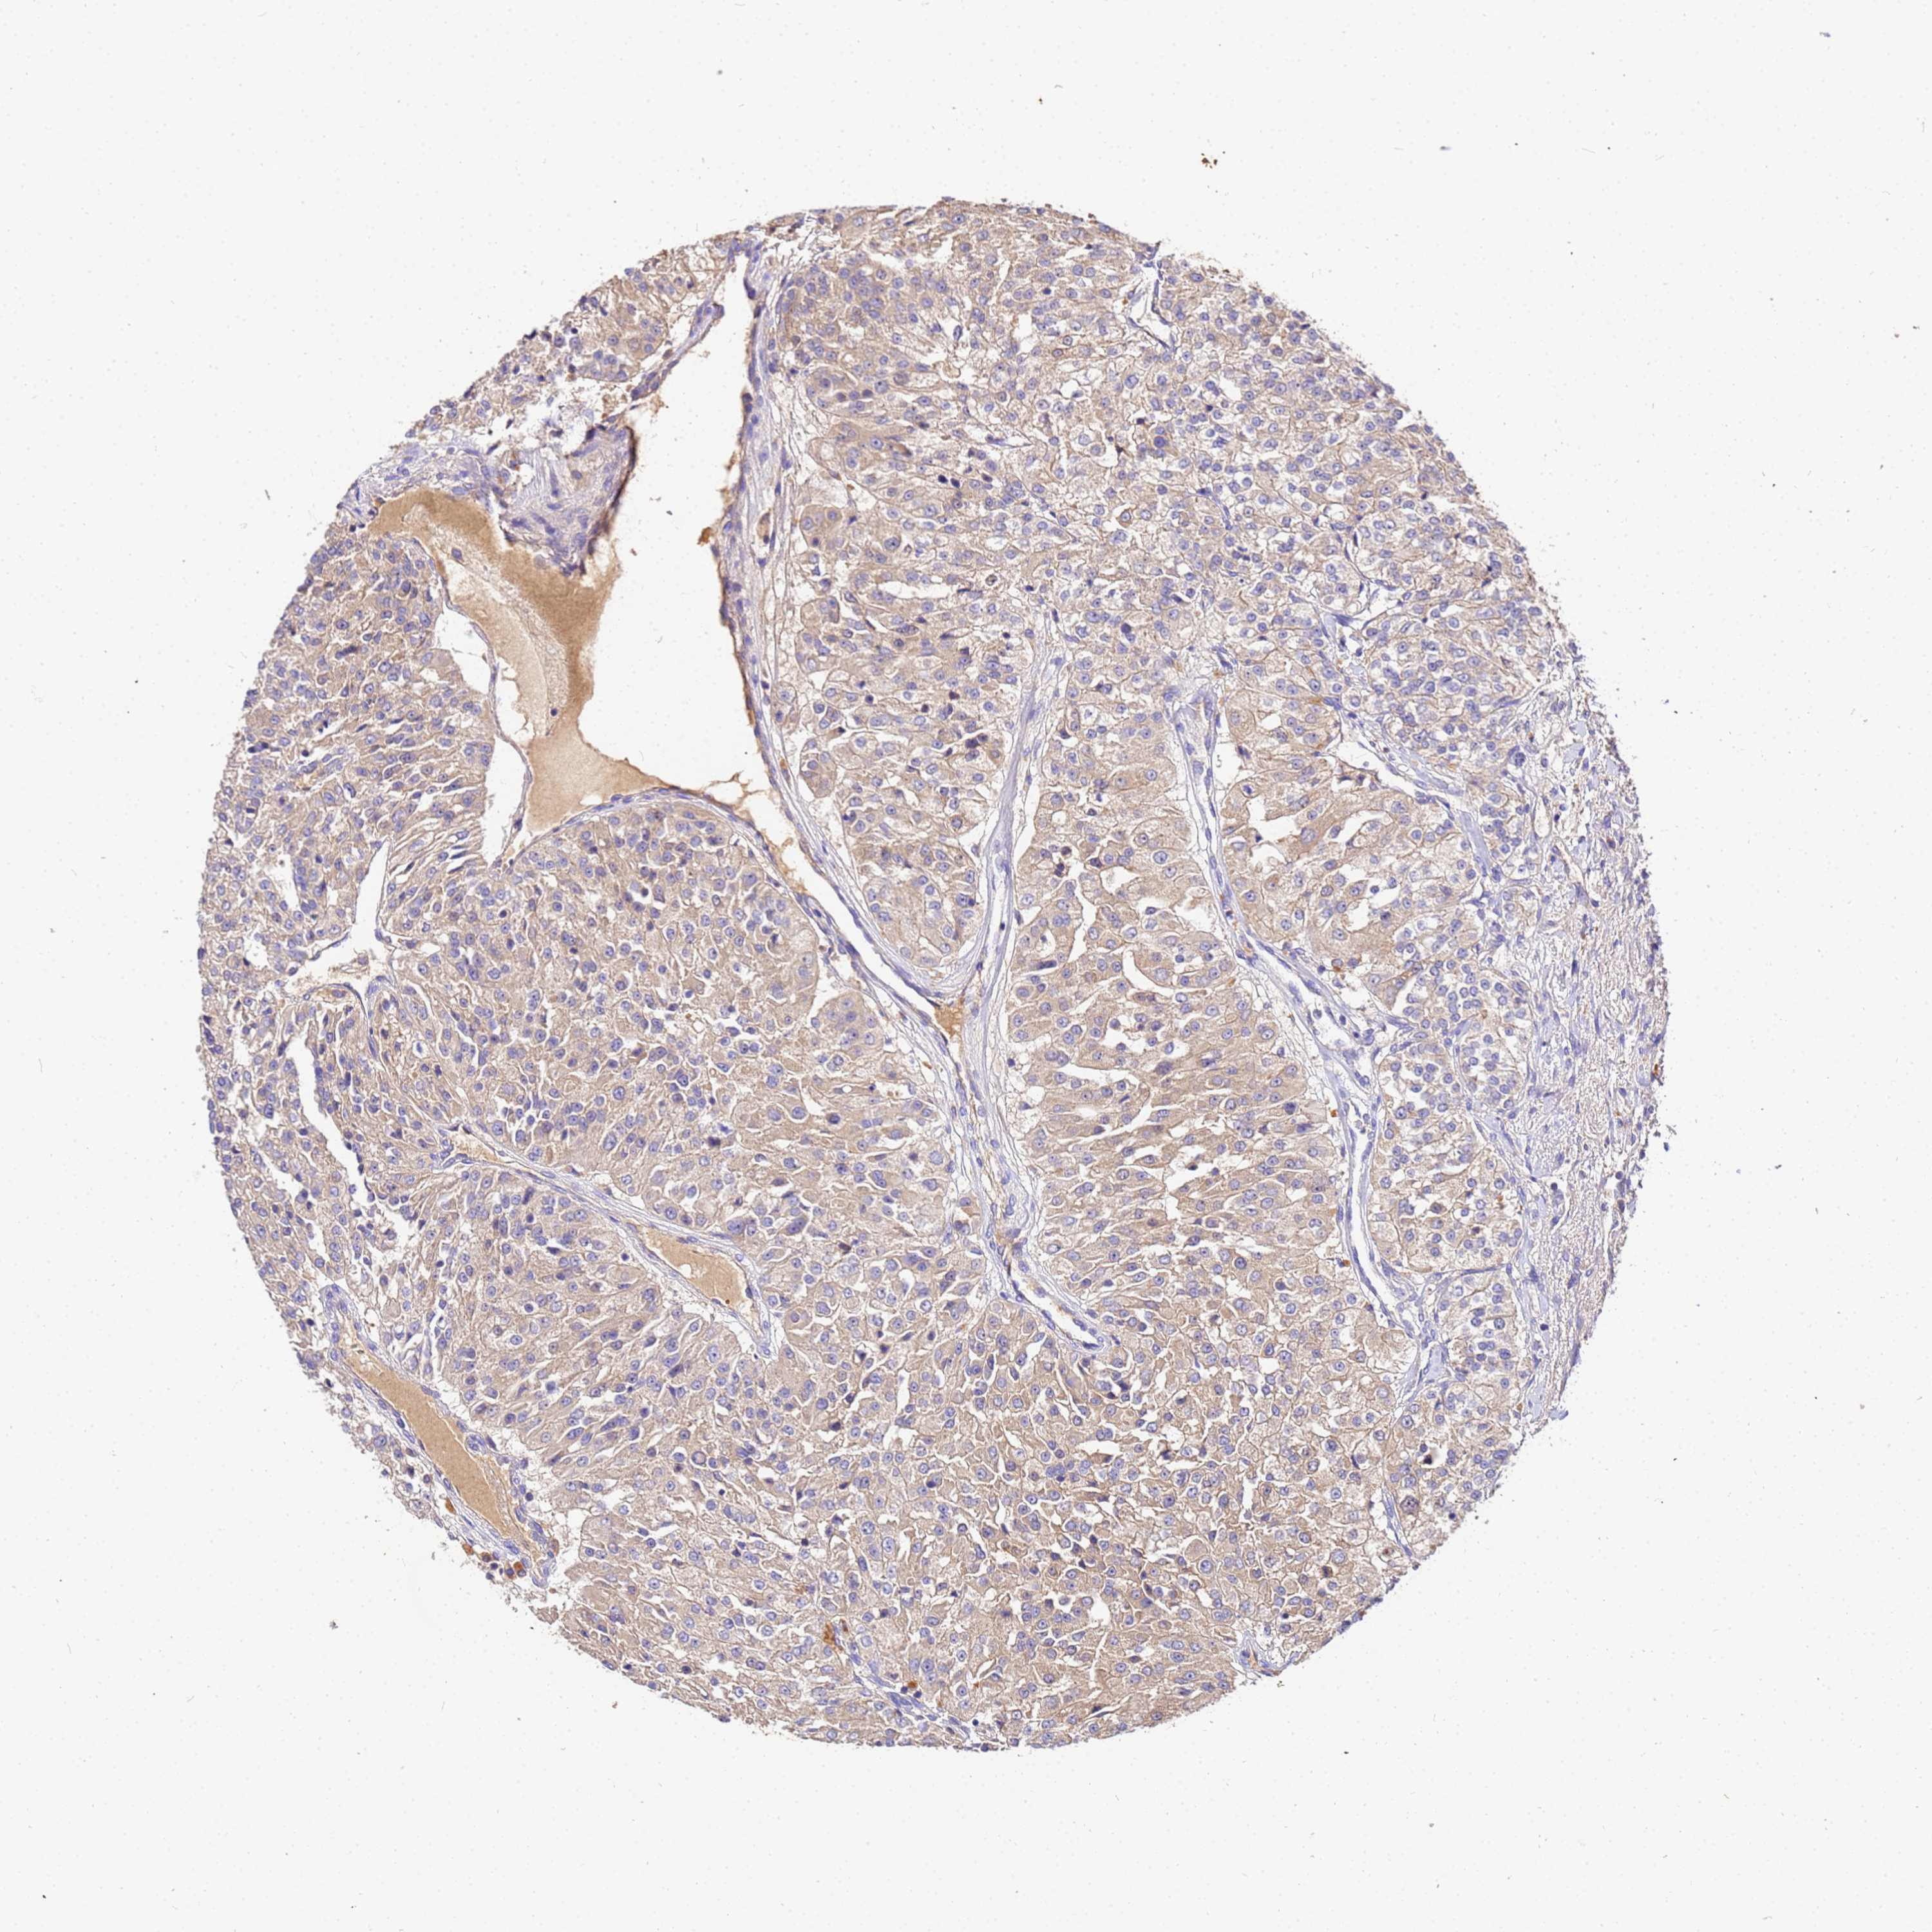

KIDNEY RENAL CLEAR CELL CARCINOMA (VALIDATION) - Interactive survival scatter ploti

The Survival Scatter plot shows the clinical status (i.e. dead or alive) for all individuals in the patient cohort, based on the same data that underlies the corresponding Kaplan-Meier plots. Patients that are alive at last time for follow-up are shown in blue and patients who have died during the study are shown in red.

The x-axis shows the expression levels (FPKM) of the investigated gene in the tumor tissue at the time of diagnosis. The y-axis shows the follow-up time after diagnosis (years). Both axes are complimented with kernel density curves demonstrating the data density over the axes. The top density plot shows the expression levels (FPKM) distribution among dead (red) and alive patients (blue). The right density plot shows the data density of the survived years of dead patients with high and low expression levels respectively, stratified using the cutoff indicated by the vertical dashed line through the Survival Scatter plot. This cutoff is automatically defined based on the FPKM cutoff that minimizes the p-score. The cutoff can be changed by dragging the vertical line or by entering a cutoff value in the square labeled "Current cut-off".

Under the Survival Scatter plot the p-score landscape (black curve; left axis) is shown together with dead median separation (red curve; right axis). Dead median separation is the difference in median mRNA expression between patients who have died with high and low expression, respectively. It is calculated as follows: median FPKM expression of dead patients with high expression - median FPKM expression of dead patients with low expression. This is intended to aid the user in visually exploring custom cutoffs and the associated p-scores and dead median separation.

Individual patient data is displayed and can be filtered by clicking on one or more of the category buttons on the top of the page. Categories describing expression level and patient information include: high, low, alive, dead, female, male and tumor stages. The scale of the x-axis can be toggled between linear and log-scale by clicking on the "x log" button. Mouse-over function shows TCGA ID, patient information and mRNA expression (FPKM) for each patient.

& Survival analysisi

Kaplan-Meier plots summarize results from analysis of correlation between mRNA expression level and patient survival. Patients were divided based on level of expression into one of the two groups "low" (under cut off) or "high" (over cut off). X-axis shows time for survival (years) and y-axis shows the probability of survival, where 1.0 corresponds to 100 percent.

MTERF1 is not prognostic in Kidney Renal Clear Cell Carcinoma (validation)

Best expression cut offi

Based on the FPKM value of each gene, patients were classified into two groups and association between prognosis (survival) and gene expression (FPKM) was examined. The best expression cut-off refers the FPKM value that yields maximal difference with regard to survival between the two groups at the lowest log-rank P-value. Best expression cut-off was selected based on survival analysis .

When clicking on this number, the vertical dashed line indicating cut-off, the interactive survival plot, and the Kaplan-Meier curve will be adjusted to show results based on the best expression cut-off.

: 10.35

P scorei

Log-rank P value for Kaplan-Meier plot showing results from analysis of correlation between mRNA expression level and patient survival.

N/A

5-year survival highi

5-year survival for patients with higher expression than the expression cutoff.

For melanoma and glioma, 3-year survival is shown.

5-year survival lowi

5-year survival for patients with lower expression than the expression cutoff.

TCGA RNA samplesi

RNA-seq data is reported as average FPKM (number Fragments Per Kilobase of exon per Million reads), generated by the The Cancer Genome Atlas (TCGA) .

Normal distribution across the dataset is visualized with box plots, shown as median and 25th and 75th percentiles. Points are displayed as outliers if they are above or below 1.5 times the interquartile range. FPKM values of the individual samples are presented next to the box plot.

Average pTPM 9.5

Number of samples 100